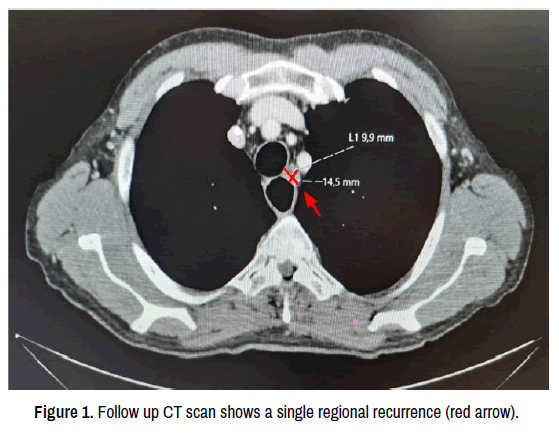

At this re-evaluation, the CT scan revealed a lymphadenopathy in the left superior mediastinum, adjacent to the origin of the ipsilateral subclavian artery, suspicious for regional disease recurrence (Figure 1). The radiological results were discussed in our multidisciplinary board, where the presence of a single site of locoregional recurrence was confirmed, with no evidence of distant metastases.

Figure 1. Follow up CT scan shows a single regional recurrence (red arrow).